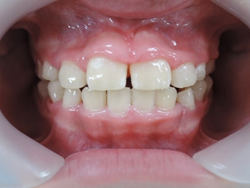

初診時より1年6カ月後 終了時(8歳8か月)

終了時より2年2カ月後(10歳11か月)

初診時より2年2カ月後

一口メモ 上顎左右の切歯が逆に咬んでいる以外はほぼ問題のない咬み合わせになりました。早期に治療を開始していなければ大変、治療に苦労する症例となっているはずでしたが改善する事が出来ました。

8歳の女子 受け口(下顎前突)

術後

いずれも、顎のラインがスッキリしています。

これは、受け口が改善して筋肉の使い方が通常に戻ったために起こった変化です。

大人ではこの変化は起こりません。

1年6ヶ月後 矯正終了時

1年6ヶ月で小学生低学年の矯正を終了します。

☆終了時(1年6ヶ月)